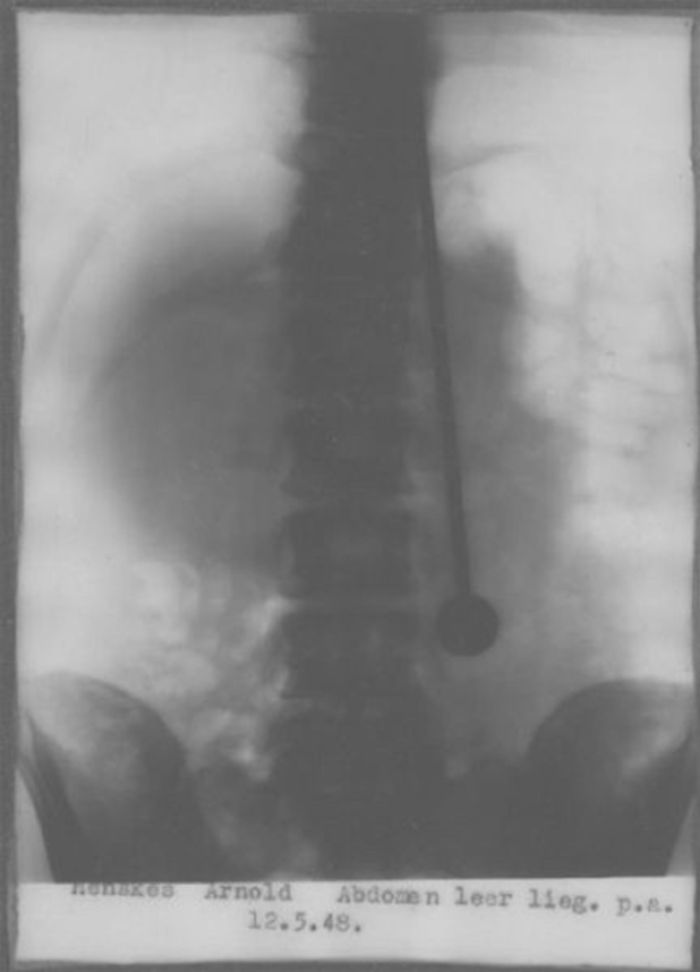

В 1947 году Мирин Дажо отправился на гастроли в Швейцарию. 31 мая 1947 года он продемонстрировал свои таланты в Цюрихском кантональном госпитале в присутствии множества докторов, врачей и журналистов. Там же были сделаны рентгеновские снимки, показывающие пронзённые шпагой внутренние органы. После изъятия шпаги кровь отсутствовала, а на теле остались лишь маленькие пятнышки. Подобные исследования были проведены также в Базеле и Берне.

Для того чтобы убедиться в отсутствии повреждения внутренних органов, Дажо сделали рентген. И легкие, и сердце были в полном порядке, несмотря на то, что в них в этот момент находилась настоящая рапира. Создавалось впечатление, будто бы орудие проткнуло насквозь не живого человека, а манекен с пластилиновыми органами. Причем уникум уверил врачей, что никакого вреда острый предмет ему не нанес, но все-таки снисходительно разрешил помазать малюсенькие отверстия в теле, оставленные рапирой дезинфицирующими средствами.

Скептики уверены, что он фокусник: "закрывает кулаком откуда выходит наконечник, закрывает рукой отверстие когда вынимает шпагу, ну и подделка рентгена. Края должны быть черными, а шпага и тело белыми (и должны быть видно ребра и внутренние органы." Но это мнение юзеров интернета, каких то документов или источников на этот счет нет.